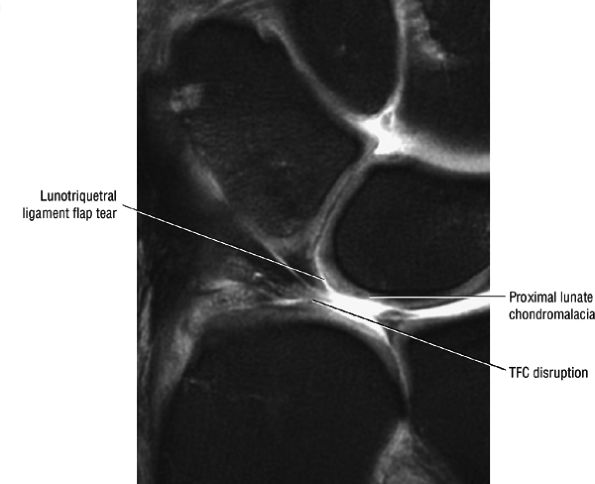

FIGURE 10.1 ● A 3D fast spoiled GRASS (FSPGR) with intra-articular contrast injected into the radiocarpal compartment. The torn lunotriquetral ligament (straight arrow) allows extension of contrast into the midcarpal compartment and the torn radial attachment of the TFC (curved arrow) directs contrast into the distal radioulnar joint. Note the superior trabecular bone detail on this image (coronal image; TR, 40.4 msec; TE, 14.5 msec; FOV, 4 cm; slice thickness, 2.0 mm; matrix, 512 × 256; flip angle, 30°).